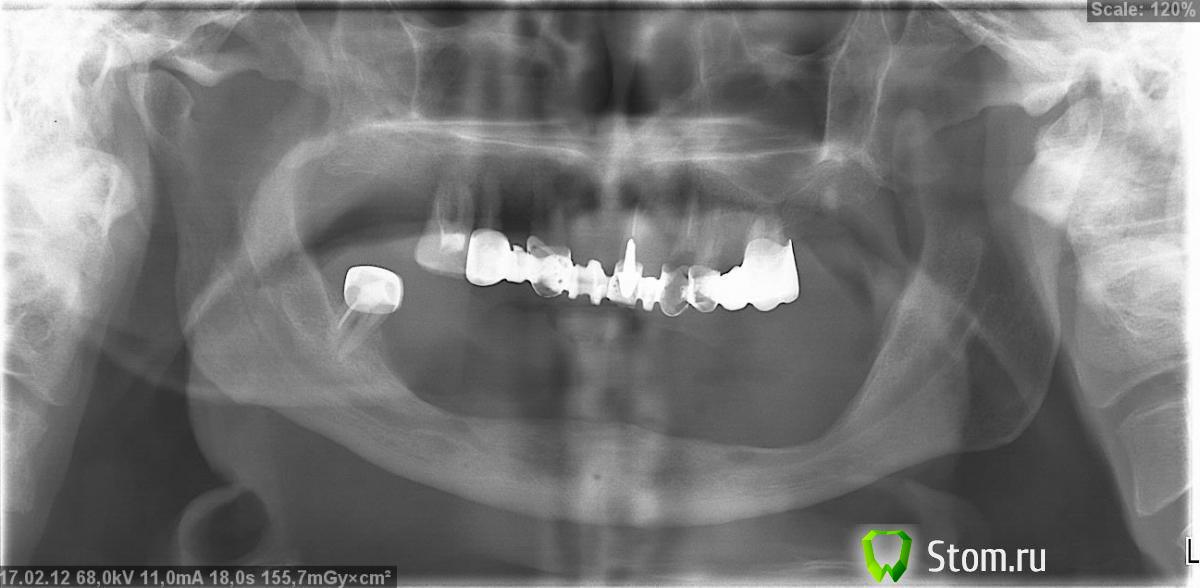

OGB Опубликовано 2 марта, 2012 Поделиться Опубликовано 2 марта, 2012 (изменено) Пациенту 72 года, съемные протезы в очередной раз вышли из строя. Состояние оставшихся зубов, судя по всему, не позволяет установить новые. До сих пор читает лекции в университете (артикуляция и т.д.). Какие есть варианты протезирования/имплантации? Имеет ли смысл имплантация в этом возрасте?Спасибо заранее. Изменено 2 марта, 2012 пользователем OGB Ссылка на комментарий

Vitasem Опубликовано 8 марта, 2012 Поделиться Опубликовано 8 марта, 2012 Верх полный съемный протез с атачменами(какие зубы останутся, какие уйдут увидится при снятии коронок. ориентировочно останутся 13 и 25), низ - перелечить 48, коронка и частичный протез.В низу, разве что 4 имплпнта для фиксации протеза. Ссылка на комментарий

Dr. Stom Опубликовано 9 марта, 2012 Поделиться Опубликовано 9 марта, 2012 (изменено) тут ничего не останется к сожалениюили 2 полных съемных или делать компьютерную томографию и на консультацию к имплантологу Изменено 9 марта, 2012 пользователем Dr. Stom Ссылка на комментарий